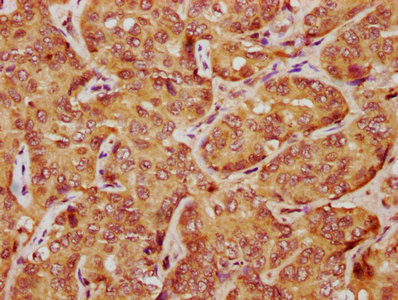

IHC image of CSB-PA012769LA01HU diluted at 1:1200 and staining in paraffin-embedded human liver cancer performed on a Leica BondTM system. After dewaxing and hydration, antigen retrieval was mediated by high pressure in a citrate buffer (pH 6.0). Section was blocked with 10% normal goat serum 30min at RT. Then primary antibody (1% BSA) was incubated at 4°C overnight. The primary is detected by a biotinylated secondary antibody and visualized using an HRP conjugated SP system.